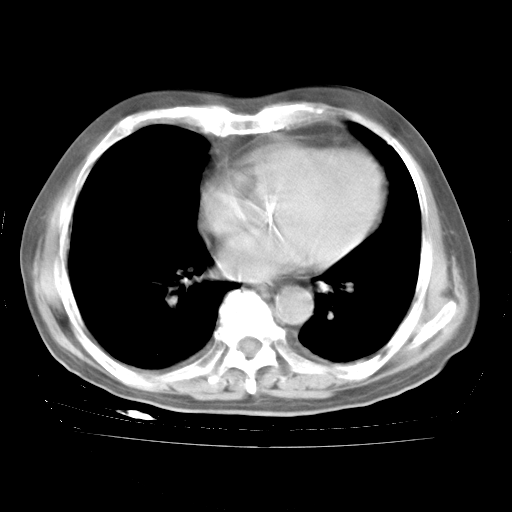

4月28日肺部CT——再次出现类似去年5月9日——透光度降低,“间质性”改变。

4月28日肺部CT——再次出现类似去年5月9日——磨玻璃样、间有“粟粒样”改变。